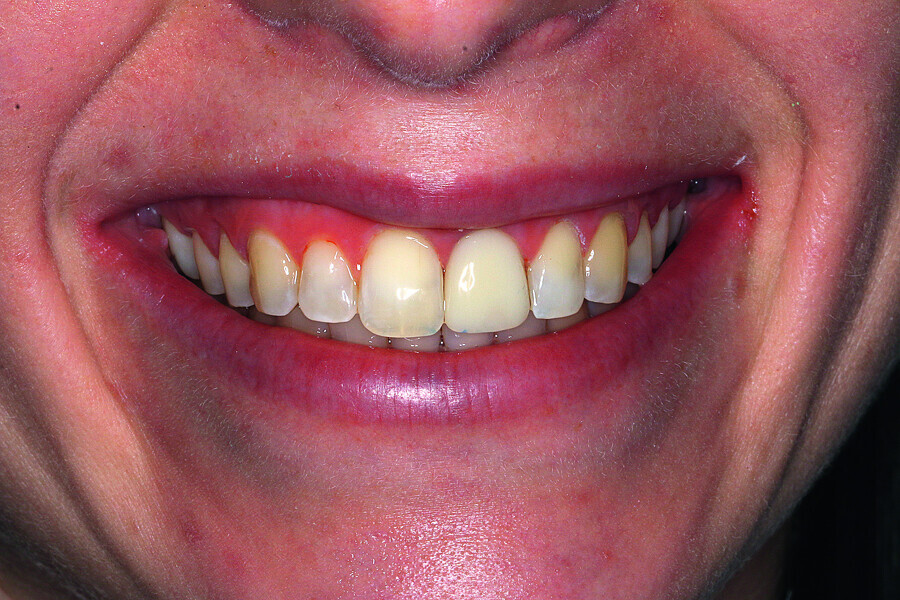

Fig. 2: Initial situation: tooth #21 exhibited marginal redness of the gingiva that bled when probed.